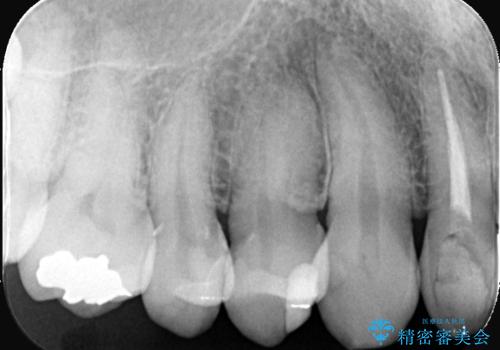

- CRの下が虫歯になっており歯が欠けている状態でした。古いCRと虫歯を除去しセラッミクインレーで治療しました。

CRが劣化し虫歯になり欠けている状態でした。歯を長持ちさせるために(再治療を減らす)セラッミクインレーで治療を行いました。

右上4のCRも劣化していてかつ形態も良くないので治療の必要性はご説明させていただきました。